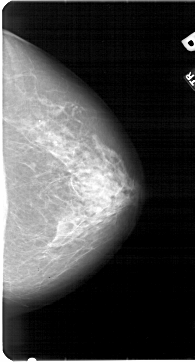

A_1954_1.RIGHT_CC

RIGHT_CC LINES 5416 PIXELS_PER_LINE 2911 BITS_PER_PIXEL 12 RESOLUTION 43.5 NON_OVERLAY